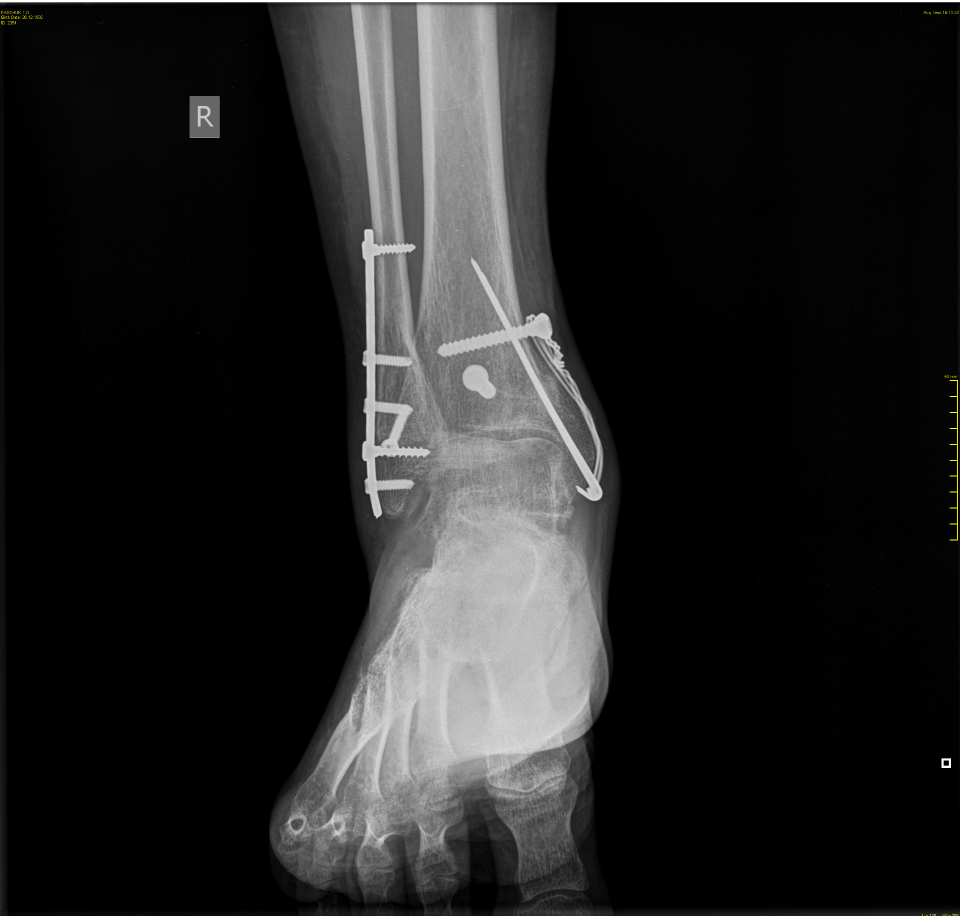

Дома сапог сняли и ножка моя странно перекосилась. Часа через два, уже в больнице выяснилось, что сломав на первом этаже ногу, я усугубила ситуацию, карабкаясь домой, и раздробила кость. В больничке меня подлатали, вставили в одну кость спицу, а другую косточку собрали и закрепили тоже какой-то конструкцией.

Вот так видят меня на просвет в аэропорту.